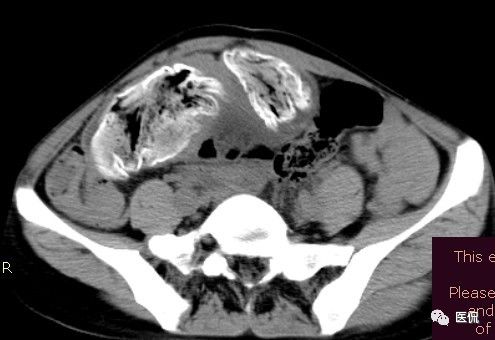

影像特点

腹腔内残留的纱布在人体内引起渗出或液化坏死并纤维包裹形成异物性脓肿(纱布瘤)。纱布瘤的影像特点:圆形或卵圆形肿块,较大,有完整包膜,薄壁,较少的情况下为厚壁,边界较完整,增强后薄膜可以持续强化。不同时期的纱布瘤可以有不同表现:早期(10个月或半年内)多表现为蜂窝状;2~5年内一般表现为囊性飘带状;10~20年之后则为实性软组织密度,包膜钙化呈钙化网状结构。手术过程中残留在人体内的医用纱布所形成的肿瘤样病变。

腹腔内遗留纱布团的影像学表现,以B超较具特征性,其主要表现为:腹腔或盆腔内特殊率减的黑色包块,后方伴有扇形衰减的声影,上窄下宽,好似一“黑色大布”,早期包块内含有不规则光团或光点,随时间延长有缩小或消失,为纱布团内气体。CT的优势在于早期常表现为软组织密度的肿块,其内可见多少不等的气泡,随时间的延长气泡逐渐被吸收减少至消失,增强扫描可见包膜不同程度强化而内容物无强化。熟悉其影像学表现,可在术前作出明确诊断。